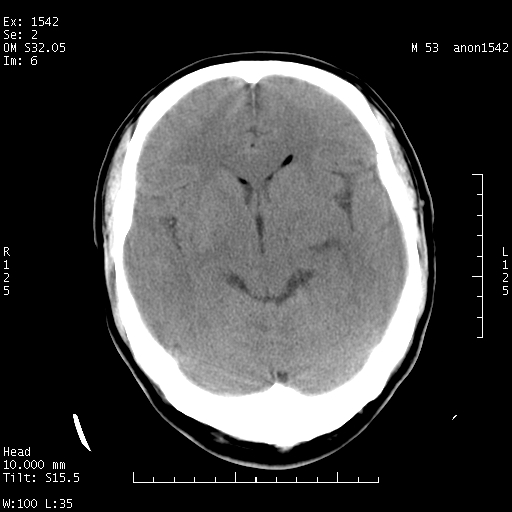

左侧鞍旁不规则低密度,此区域和侧脑室有液平。若无外伤史。考虑左侧鞍旁表皮样囊肿自发破溃。

鞍旁颞叶低密度灶.其中散在空气影.还有侧脑室.是否考虑脑脓肿(请提供病史情况)

1.支持考虑左侧鞍旁表皮样囊肿自发破可能;

考虑左侧鞍旁表皮样囊肿自发破溃。